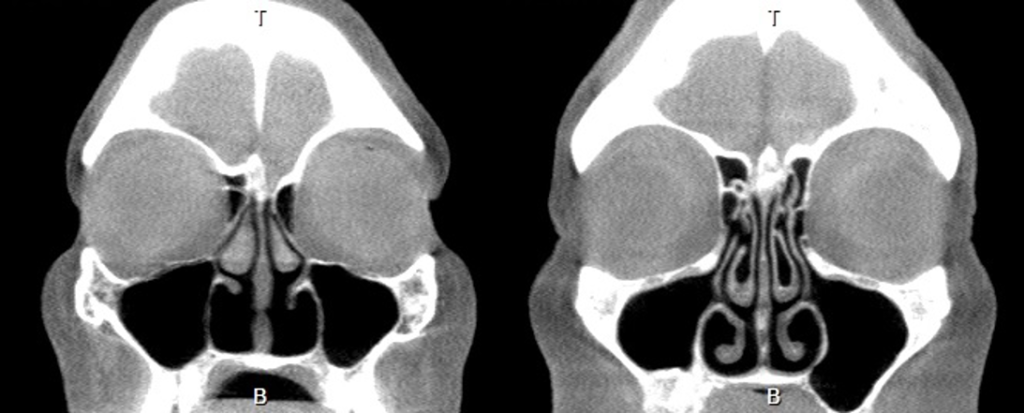

Imaging Techniques:

In some cases, the doctor may order a CT scan (computed tomography) or MRI (magnetic resonance imaging) to better assess the structure of the nose and sinuses. These imaging techniques can provide detailed views of the structural changes in the nose and the condition of the turbinates. These tests can also help differentiate ENS from other causes of nasal obstruction.